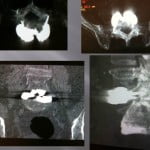

Vertebroplasty in the case of a fracture on posterior material implants

This type of vertebral fracture raises the problem of the entrance way and of the reduced visibility in lateral scopy of the filling of the secondary vertebral at the artrodesis material. The scannographic volume acquisition and the spotting has a large importance to guide the progress of the trocar without being blocked by the arthrodesis screws. The trocar path is outside the screws. An iterative scanner control checks the correct lateral position and the progression in the vertebrae to position at the level of the third anterior and third posterior. The filling is performed in the same way as standard vertebroplasty, the visualization of the cement by continuous lateral scopy is blocked by the osteosynthesis material, for this reason the injection must be done very carefully by alternatively controlling with scanner cuts the correct diffusion of the cement. The scanner control can also be blocked by the artifacts of the osetosynthesis material. Moreover in the cases of osteopenic fractures on arthrodesis, a low density line can exist around the screws showing a potential mobility of the material. In this case, the scanner guide can be very useful to position the tip of the trocar in front of this line. Thus, the vertebroplasty has the additional function to fix the intra vertebral corporeal arthrodesis.

Only the scannographic cuts allow to confirm the correct diffusion around the screws. The clinical results in out series are stackable to the vertebroplasties in the frame of the hyperalgic osteopenic fractures.